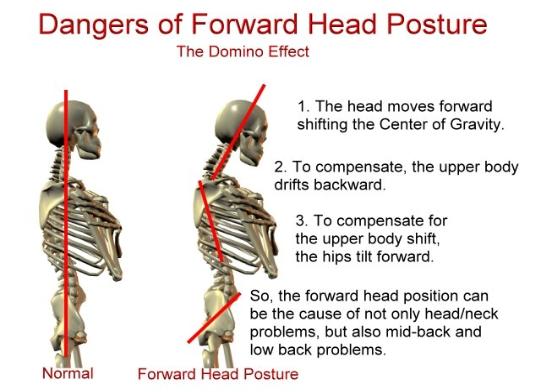

Address your pain

by addressing your

posture

Posture Correction

Acute and Chronic Pain

Muscle Pain

Joint Pain

Headaches

Migraine

Disc Pain

Injury

Scoliosis